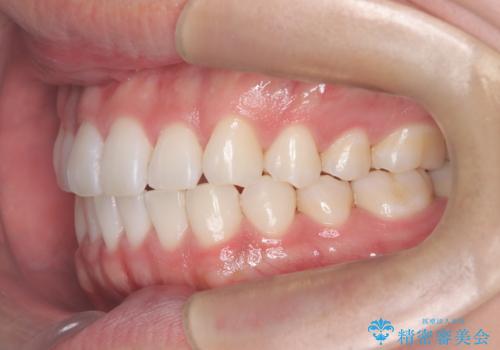

インビザラインで叢生の改善を行いました。

歯は抜かずに、拡大と少しのIPRで並べました。

矯正期間は半年です。

綺麗な歯並びを手に入れ大変ご満足していただきました。